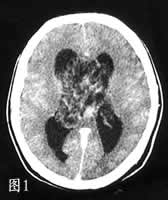

CT示双侧脑室肿物,呈泡沫状,实性部分有增强,双侧脑室轻度积水(图1)。MRI上肿瘤实性部分T1WI与T2WI均与白质信号相近,中度增强(图2、3),多囊内呈水样信号。